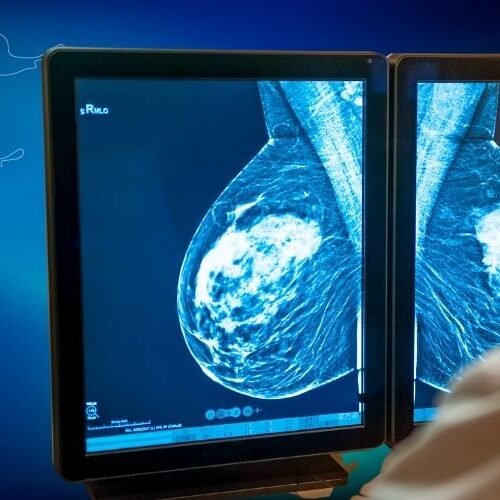

Meme cerrahisi, kanser tedavisinde meme koruyucu cerrahi ve mastektomi gibi işlemleri içerir. Ayrıca iyi huylu kitlelerin çıkarılması, meme rekonstrüksiyonu ve estetik müdahalelerle meme sağlığını ve görünümünü iyileştirmeyi hedefler.